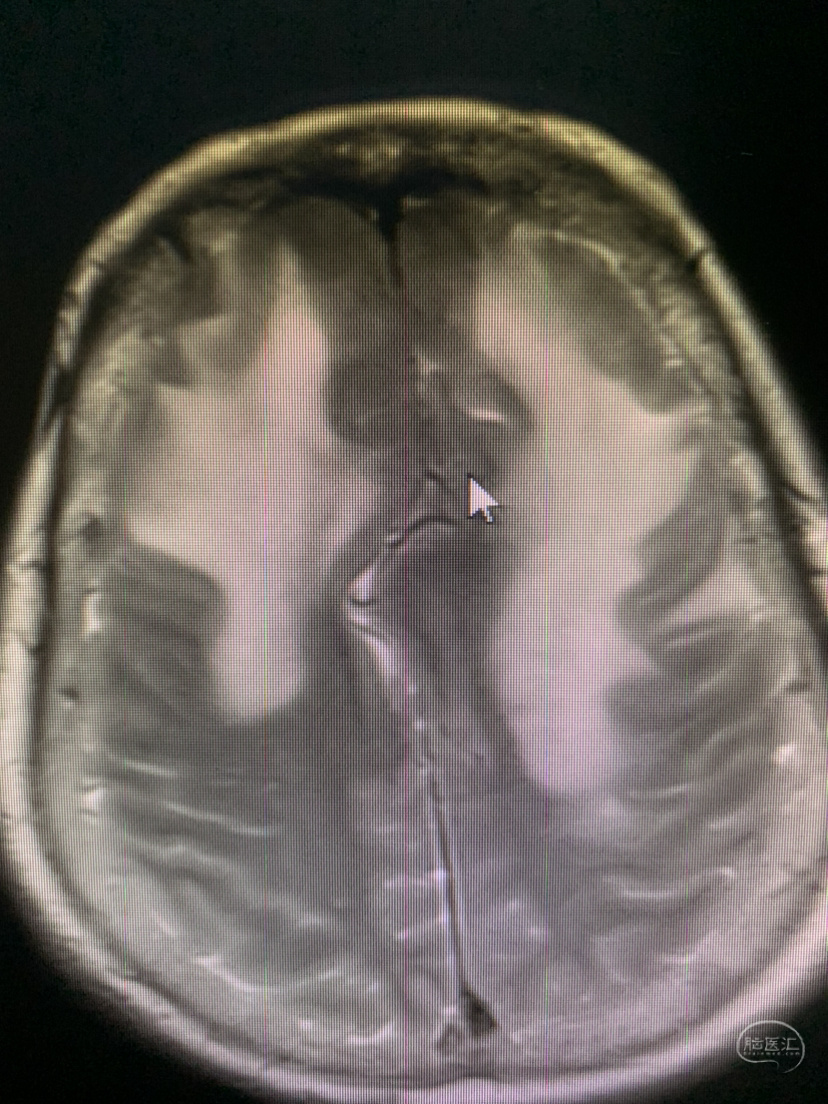

术前术后对比